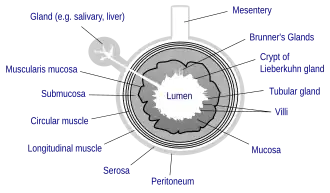

General structure of the gut wall showing the submucosa.

General structure of the gut wall showing the submucosa.